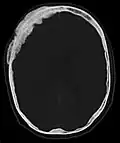

-

Axiale Computertomografie einer osteoplastischen Metastase im Schädelknochen eines Patienten mit Prostatakarzinom. Deutlich ist die Ausdehnung der Metastase über die ursprünglichen Knochengrenzen hinaus zu erkennen. -

Im Vergleich dazu eine Computertomografie osteolytischer Metastasen in den Schädelknochen einer Patientin mit Mammakarzinom. Zu sehen ist eine größere Osteolyse frontal und mehrere kleinere. -